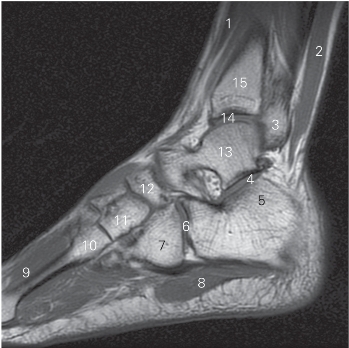

图5-58 经踝关节外踝的矢状断层MR T1加权图像

1 趾长伸肌 extensor digitorum longus

2 腓骨长、短肌 peroneus longus and brevis

3 外踝 lateral malleolus 4 距下关节 subtalar joint

5 跟骨 calcaneus 6 跟骰关节 calcaneocuboid joint

7 骰骨 cuboid bone 8 趾短屈肌 flexor digitorum brevis

9 骨间背侧肌 dorsal interossei 10 第三楔骨 3rd cuneiform bone

11 外侧楔骨 lateral cuneiform bone 12 足舟骨 navicular bone

13 距骨 talus 14 踝关节 ankle joint

15 胫骨 tibia